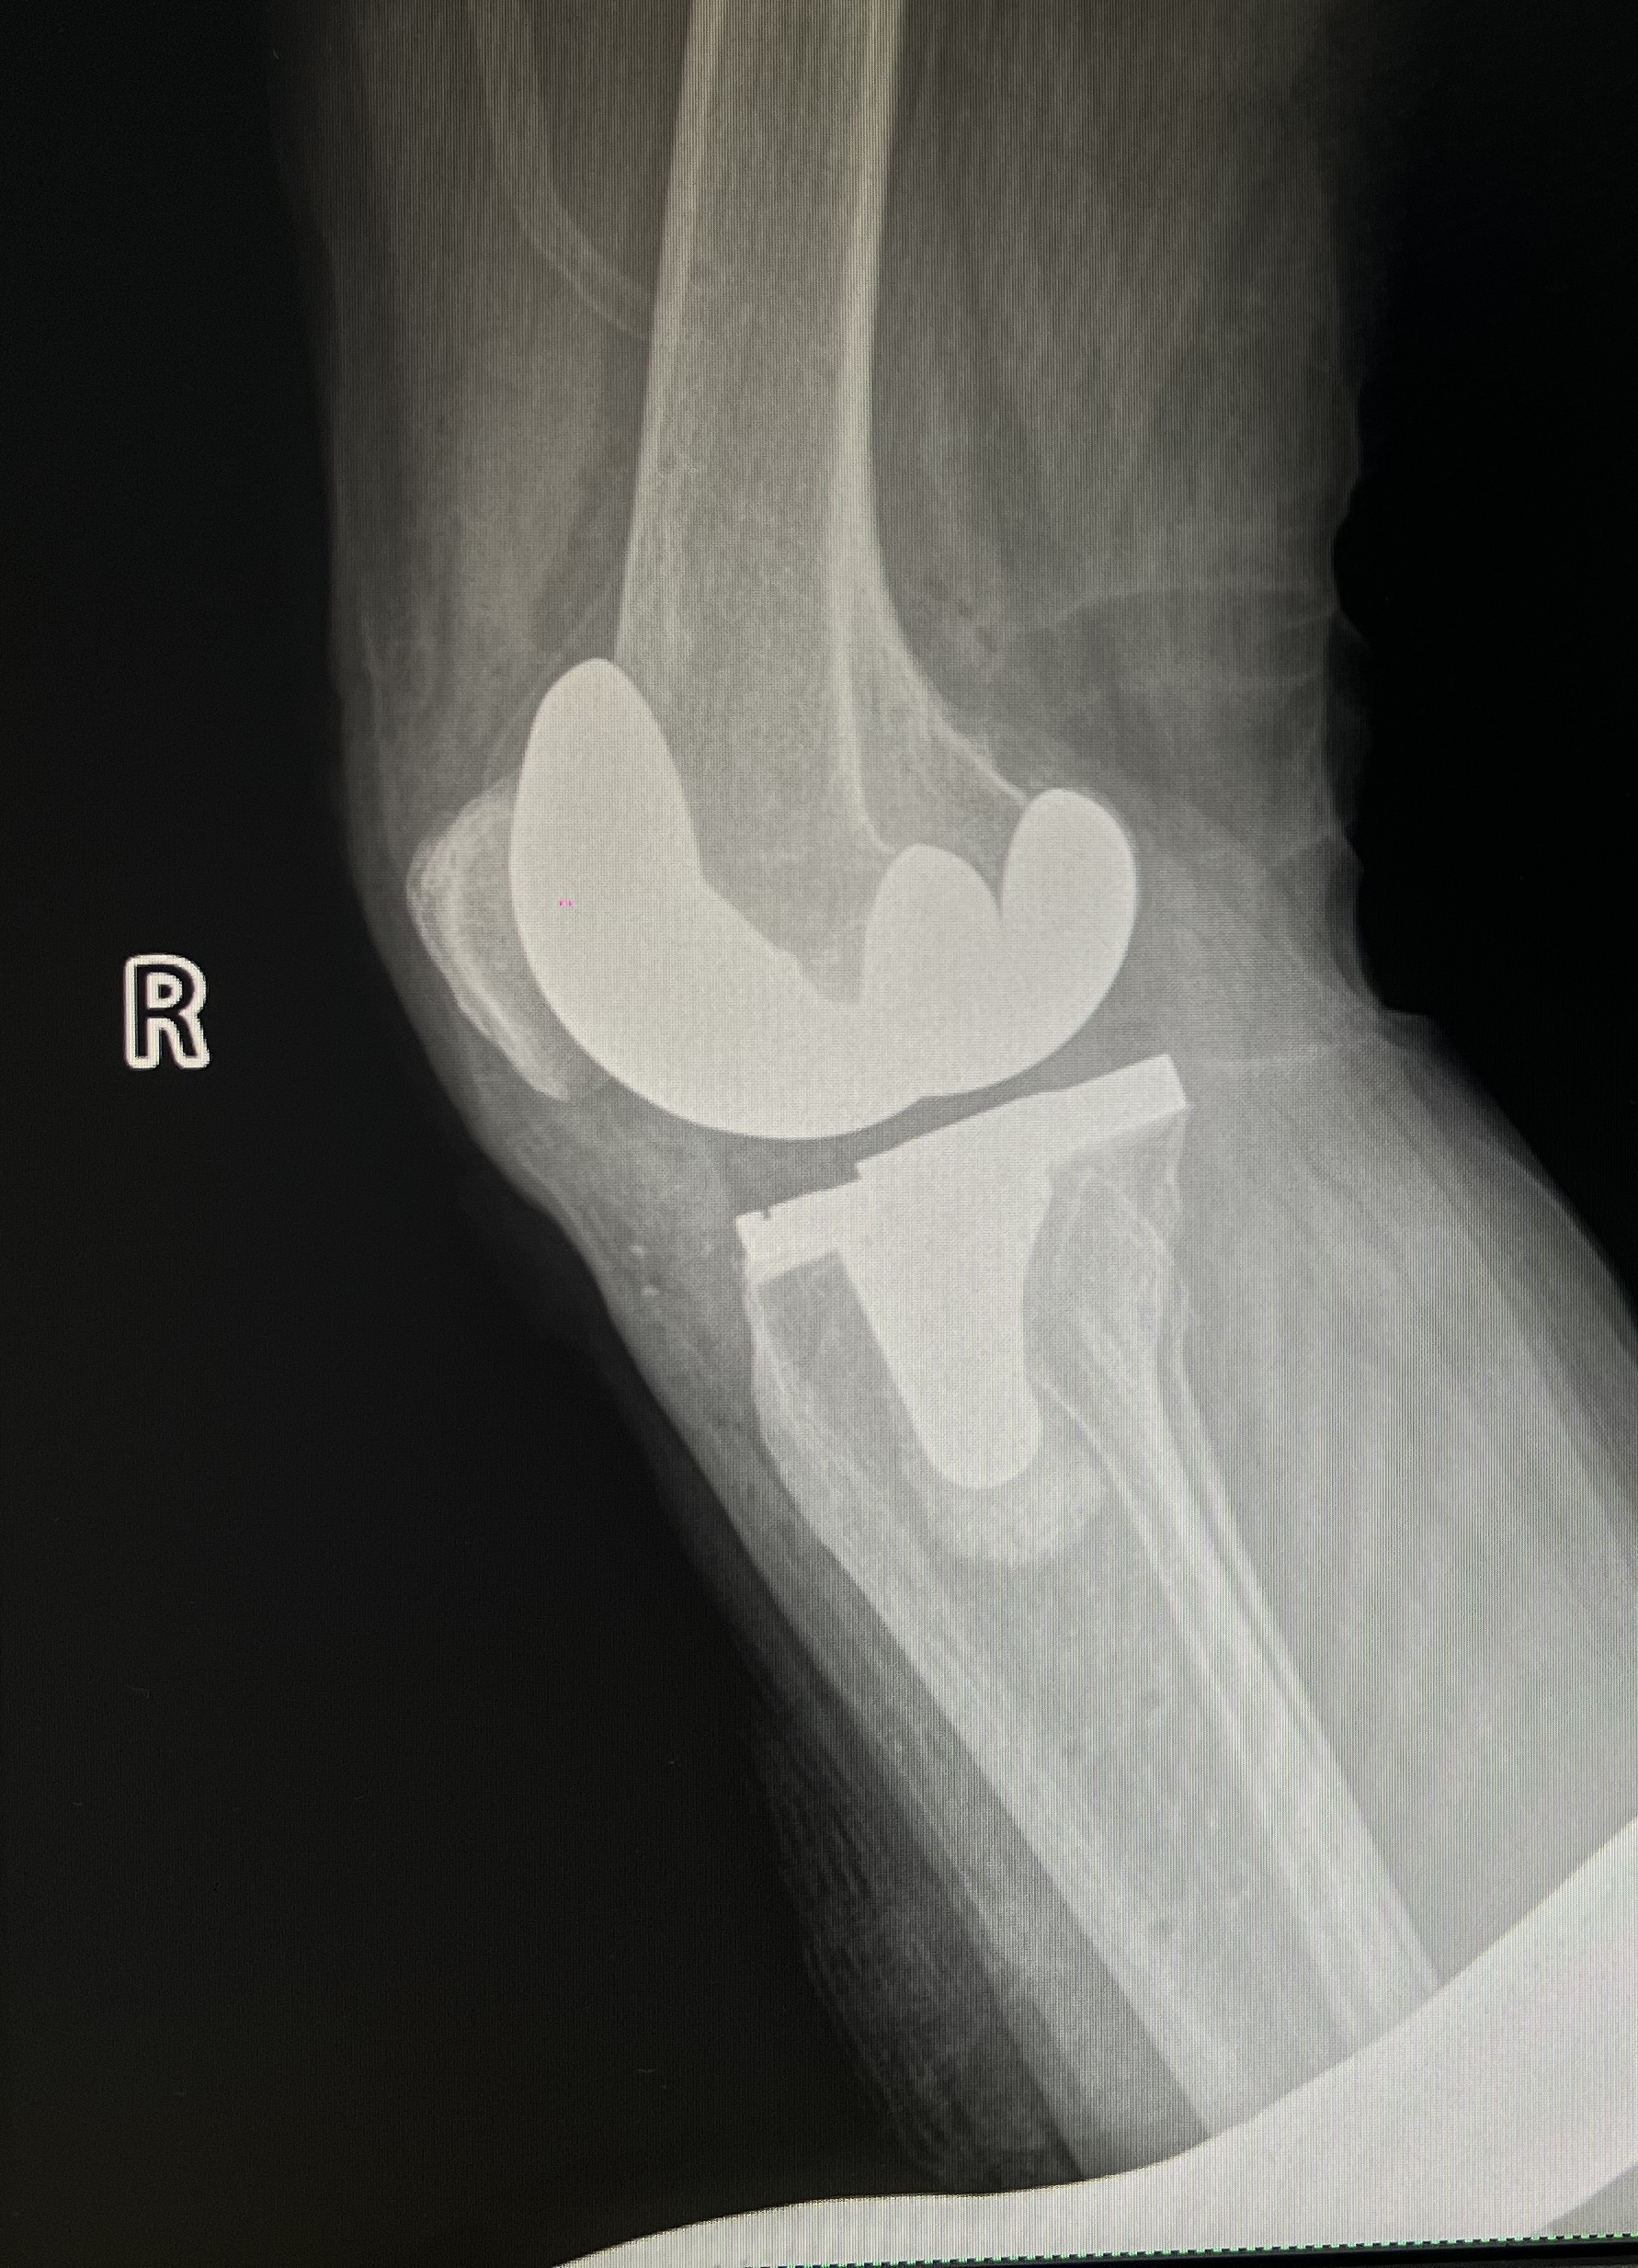

整個(gè)手術(shù)流程高效快捷,術(shù)中出血量?jī)H200毫升。與傳統(tǒng)膝關(guān)節(jié)置換術(shù)相比,鴻鵠®機(jī)器人能夠避免術(shù)中的髓腔定位,術(shù)中無髓內(nèi)桿植入,大大降低了出血量以及手術(shù)損傷,減少術(shù)后并發(fā)癥的發(fā)生,有助于患者盡早恢復(fù)。術(shù)后測(cè)量顯示,實(shí)際截骨量、下肢力線都與術(shù)前規(guī)劃的數(shù)值完全一致,實(shí)現(xiàn)了TKA手術(shù)更精準(zhǔn)、安全、高效的完成。

▲患者術(shù)后膝關(guān)節(jié)正位片(左) 患者術(shù)后膝關(guān)節(jié)側(cè)位片(右)